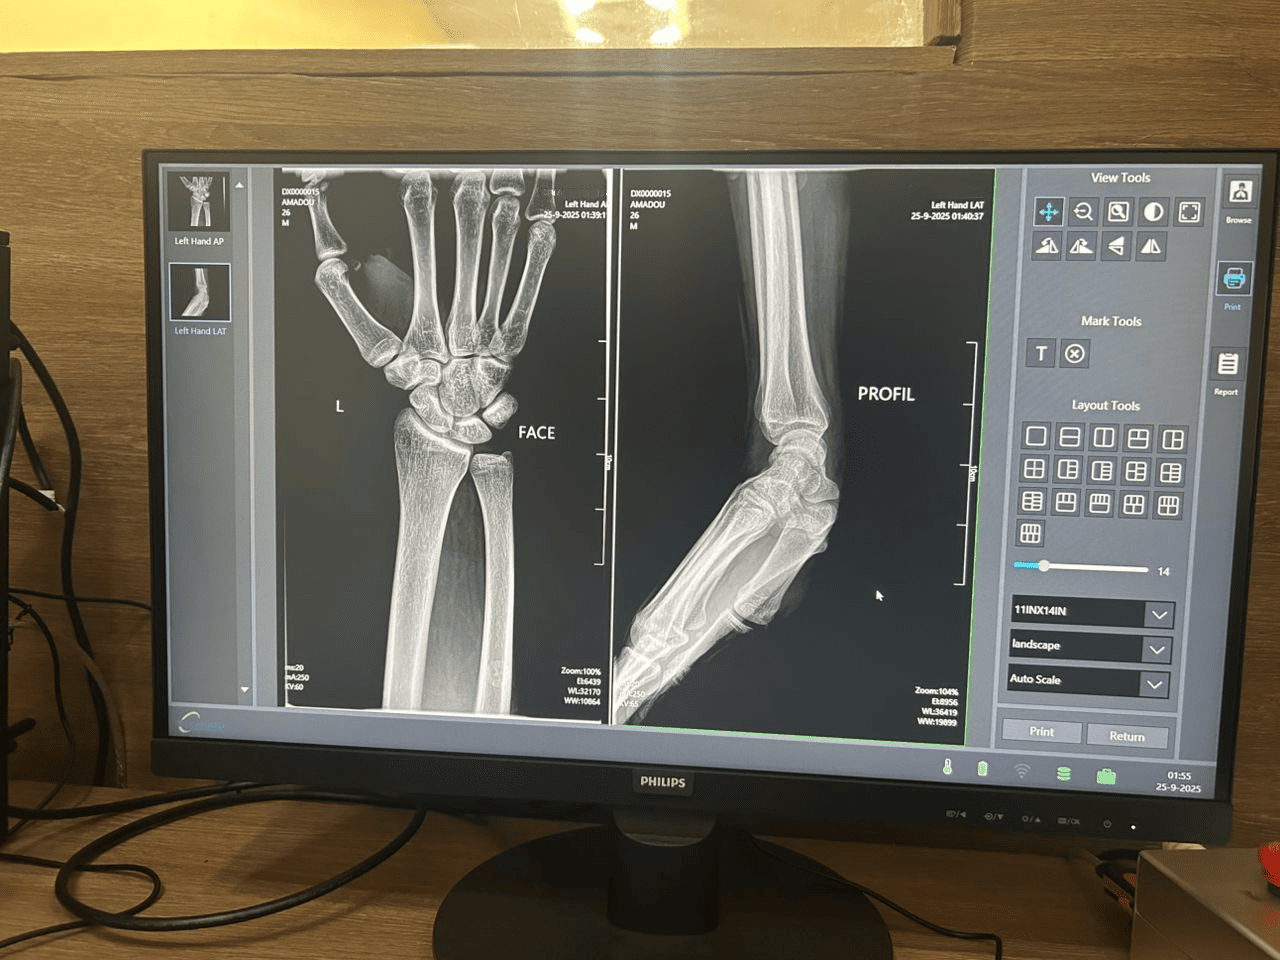

En diagnostisk testskanning med høy klarhet utført av Michael i Niger, som viser den overlegne bildeoppløsningen og programvarekalibreringen til røntgensystemet MX-DR500A10.

Trinn 4: Endelig systemkalibrering og testing

Den siste fasen var strenge tester. Michael kalibrerte programvaren, finjusterte bildeinnstillingene og kjørte testskanninger. Dette sikrer at pasienter i Niger får  høy  diagnostisk klarhet.